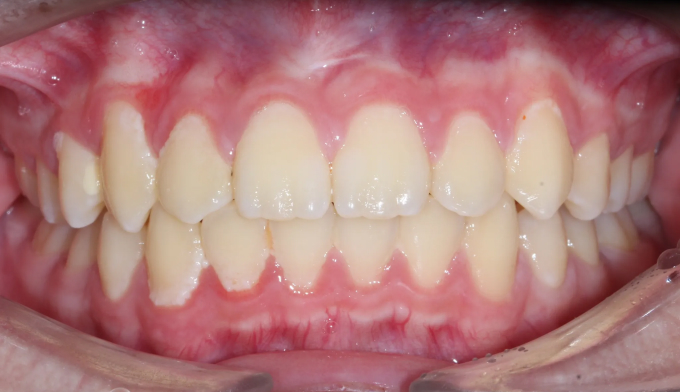

이번 케이스에서는 위쪽 송곳니의 맹출경로이상, 아래쪽 작은어금니는 작은 물혹으로 인해 맹출 경로에 문제가 생겨 교정을 진행한 경우입니다.

물혹을 제거하고 치아 교정장치를 부착하여 간단히 배열하였습니다.

총 교정기간은 11개월 입니다.